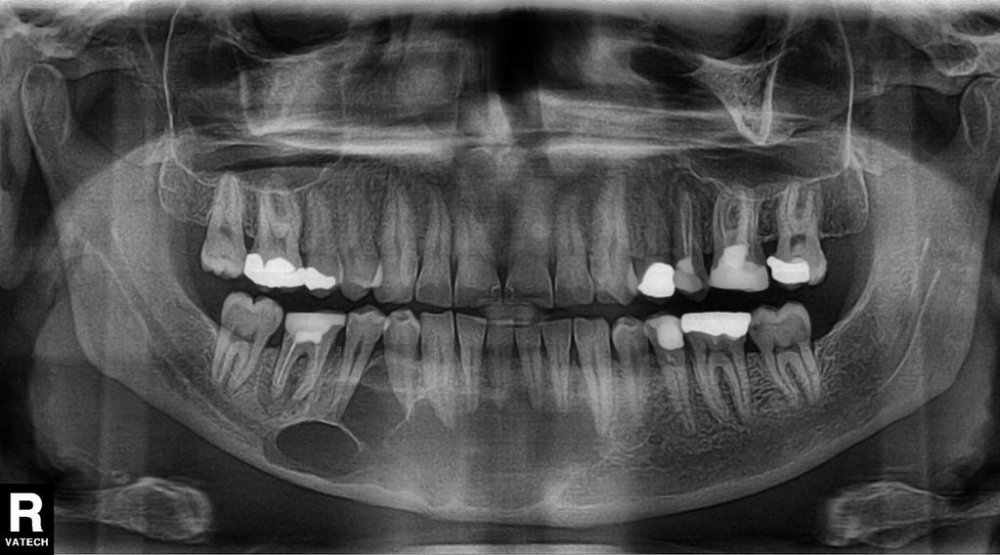

İnkşafı və böyüməsi tədricən baş verdiyindən, bu proses pasiyent tərəfindən demək olar ki hiss edilmir. Yalnız törəmənin ciddi ölçülərə çatması nəticəsində və ya iltihablanması nəticəsində meydana çıxan kliniki əlamətlər nəticəsində aşkarlanır. Əksər hallarda isə çəkilən diş və çənə rentgen şəkillərində təsadüfən rast gəlinir.

Törəmələrin müalicəsi onun növünə, yerləşməsinə, ölçüsünə, pasiyentin yaş və sağlamlıq durumuna görə seçilir və icra olunur. Müalicə prinsipi bütün hallarda nəticə etibarilə, törəmənin kənarlaşdırılmasına əsaslanır. Müalicə çox zaman yerli ağrısızlaşdırma altında bəzən isə (məsələn, böyük ölçülü kistlərin müalicəsində) ümumi ağrısızlaşdırma altında aparılır. Müalicənin gecikdirilməsi və ya təxirə salınması kistlərin daha da böyüməsinə, nəticədə ciddi miqdarda sümük itkisinə səbəb olur. Müalicənin natamam aparılması leziyonun yenidən təkrarlanmasına (residiv) səbəb ola bilir.